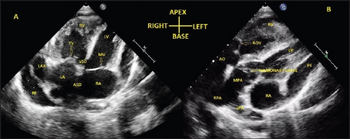

a) Transthoracic echo in apical 4-chamber view shows inverted atria b) D-transposition of great arteries